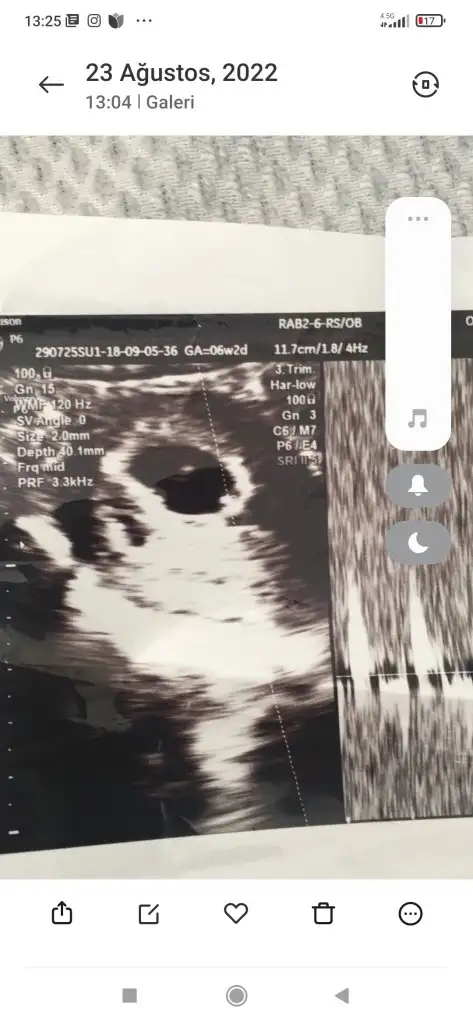

Bakın bunlarda iki kızımın teoriye göre kız değil mi

Eklentiler

• Screenshot_2022-09-16-13-24-56-504_com.miui.gallery.webp

Screenshot_2022-09-16-13-24-56-504_com.miui.gallery.webp

18,2 KB · Görüntüleme: 49